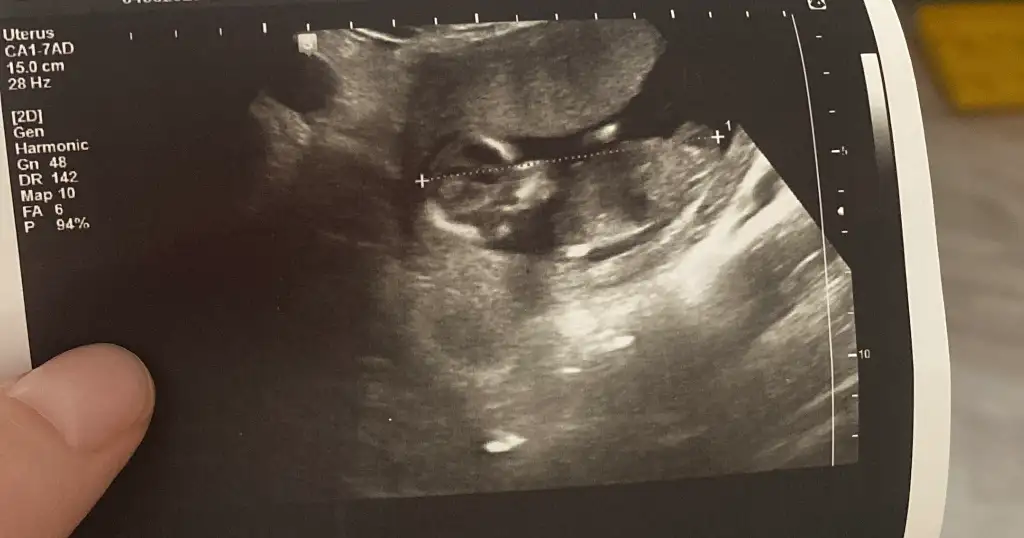

Rica ederim canım 😊 az çok anlıyorum diyelim bir de benim bebişle karşılaştırdım bana doktor muhtemelen kız ama nipt testi sonucunda net öğrenirsiniz dedi senin gerçi nub çok belirgin değil ama kese şekline göre erkek görünüyor 🥰

Sizce bizimki🌸